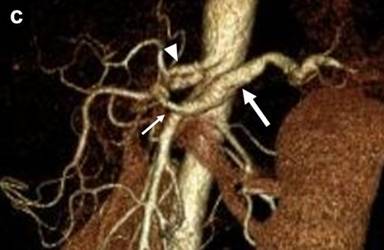

Bleeding from the papilla of Vater was not evident with upper gastrointestinal endoscopy on the day of admission. Conservative treatment was performed for the acute pancreatitis because the patient was hemodynamically stable. The epigastric pain and the serum amylase level improved after conservative treatment. During hospitalization, however, the patient developed the same epigastric pain as that usually experienced before melena, and the serum amylase level was found to be 243 U/L. We performed emergency upper gastrointestinal endoscopy to confirm the diagnosis of hemosuccus pancreaticus. Bloody pancreatic juice was observed exuding from the papilla of Vater (Figure 2). We concluded that the recurrent episodes of epigastric pain and melena had been caused by hemosuccus pancreaticus. There were no clinical or laboratory findings suggestive of arteriosclerosis or vasculitis, and diagnostic imaging showed no evidence of chronic pancreatitis or pancreatic pseudocyst. We therefore considered that the splenic aneurysm was due to segmental arterial mediolysis. We planned transcatheter arterial coil embolization for the splenic aneurysm, and the patient was discharged. However, he was re-admitted before the scheduled embolization because of sudden epigastric pain and, when tested, his serum amylase level was found to be 631 U/L. CECT revealed leakage of contrast medium into the main pancreatic duct from the aneurysm, along with dilatation of the upstream main pancreatic duct (Figure 3ab).

Figure 3. a. Contrast-enhanced computed tomography (CECT) revealing a leakage of contrast medium into the main pancreatic duct from a fusiform aneurysm of the middle-distal splenic artery (small arrow), along with dilatation of the upstream main pancreatic duct (large arrow). b. 3D-CT angiography showing a leakage of contrast medium from a fusiform aneurysm of the middle-distal splenic artery (arrow). |